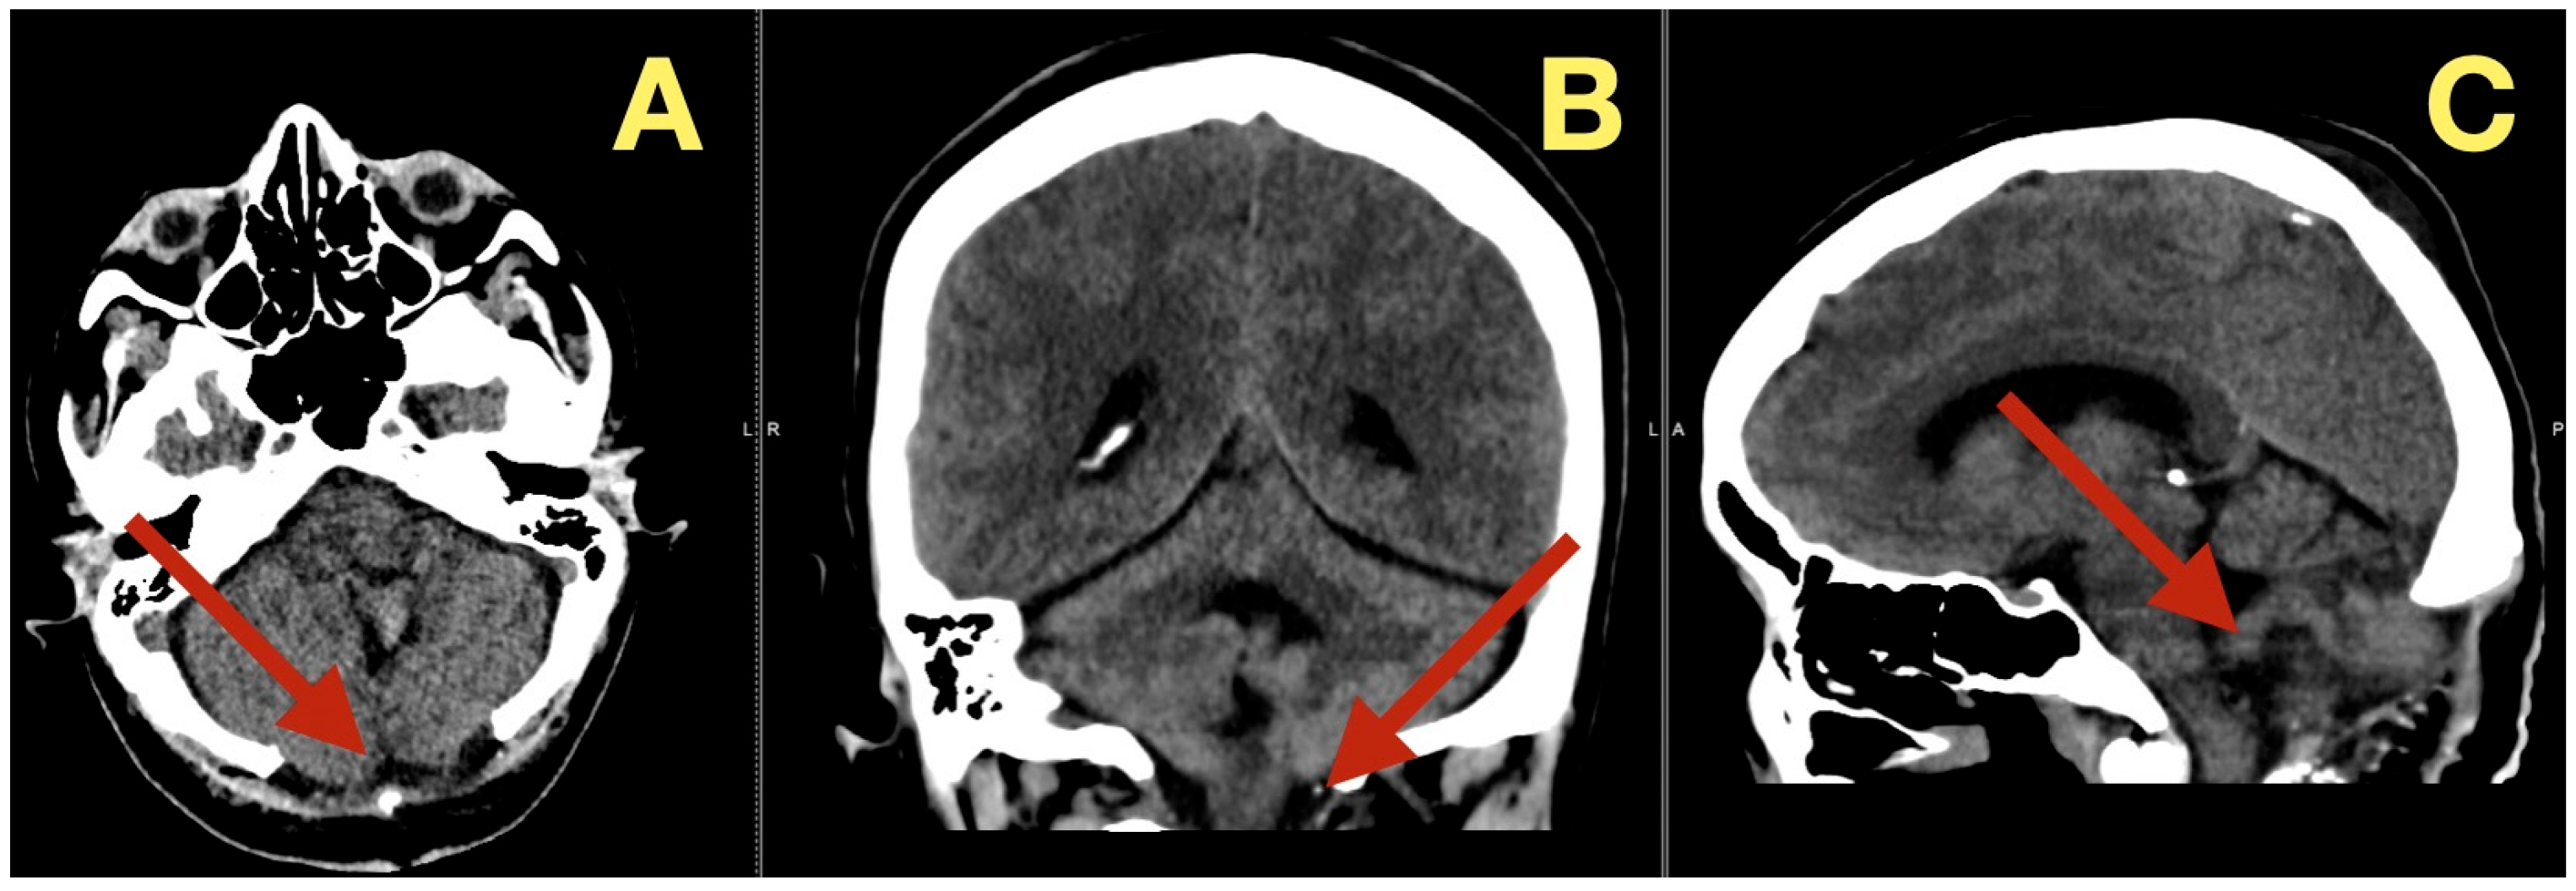

CT scans completed on the first post-operative day (Figure 3) were utilized to exclude hemorrhage and assess early ventricular diameter; they indicated posterior fossa re-expansion, full reopening of the fourth ventricle, normal brainstem convexity, and no early hydrocephalus. A second CT scan completed 7 days post-operatively (Figure 4) verified stable ventricular and outlet patency and excluded late onset hydrocephalus. The one month follow-up CT scan (Figure 5) provided a baseline for long-term comparisons. Later surveillance relied upon MRI including DWI to exclude diffusion-positive residual or recurrence.

Figure 3.

Immediate postoperative CT scan. (A): Axial CT showing full decompression of the fourth ventricle and restoration of normal CSF circulation (arrow). (B): Coronal CT demonstrating complete midline re-expansion with absence of residual mass (arrow). (C): Sagittal CT confirming brainstem relaxation and normalization of posterior-fossa anatomy (arrow).

Figure 4.

One-week postoperative CT scan. (A): Axial CT demonstrating a clean surgical cavity with complete re-expansion of the fourth ventricle and normal CSF flow through the foramen of Magendie (arrow). (B): Coronal CT showing preserved midline symmetry and restored perimedullary cisterns without evidence of fluid collection or residual density (arrow). (C): Sagittal CT confirming normalization of posterior-fossa configuration, intact vermian curvature, and patent foramina of Luschka (arrow).